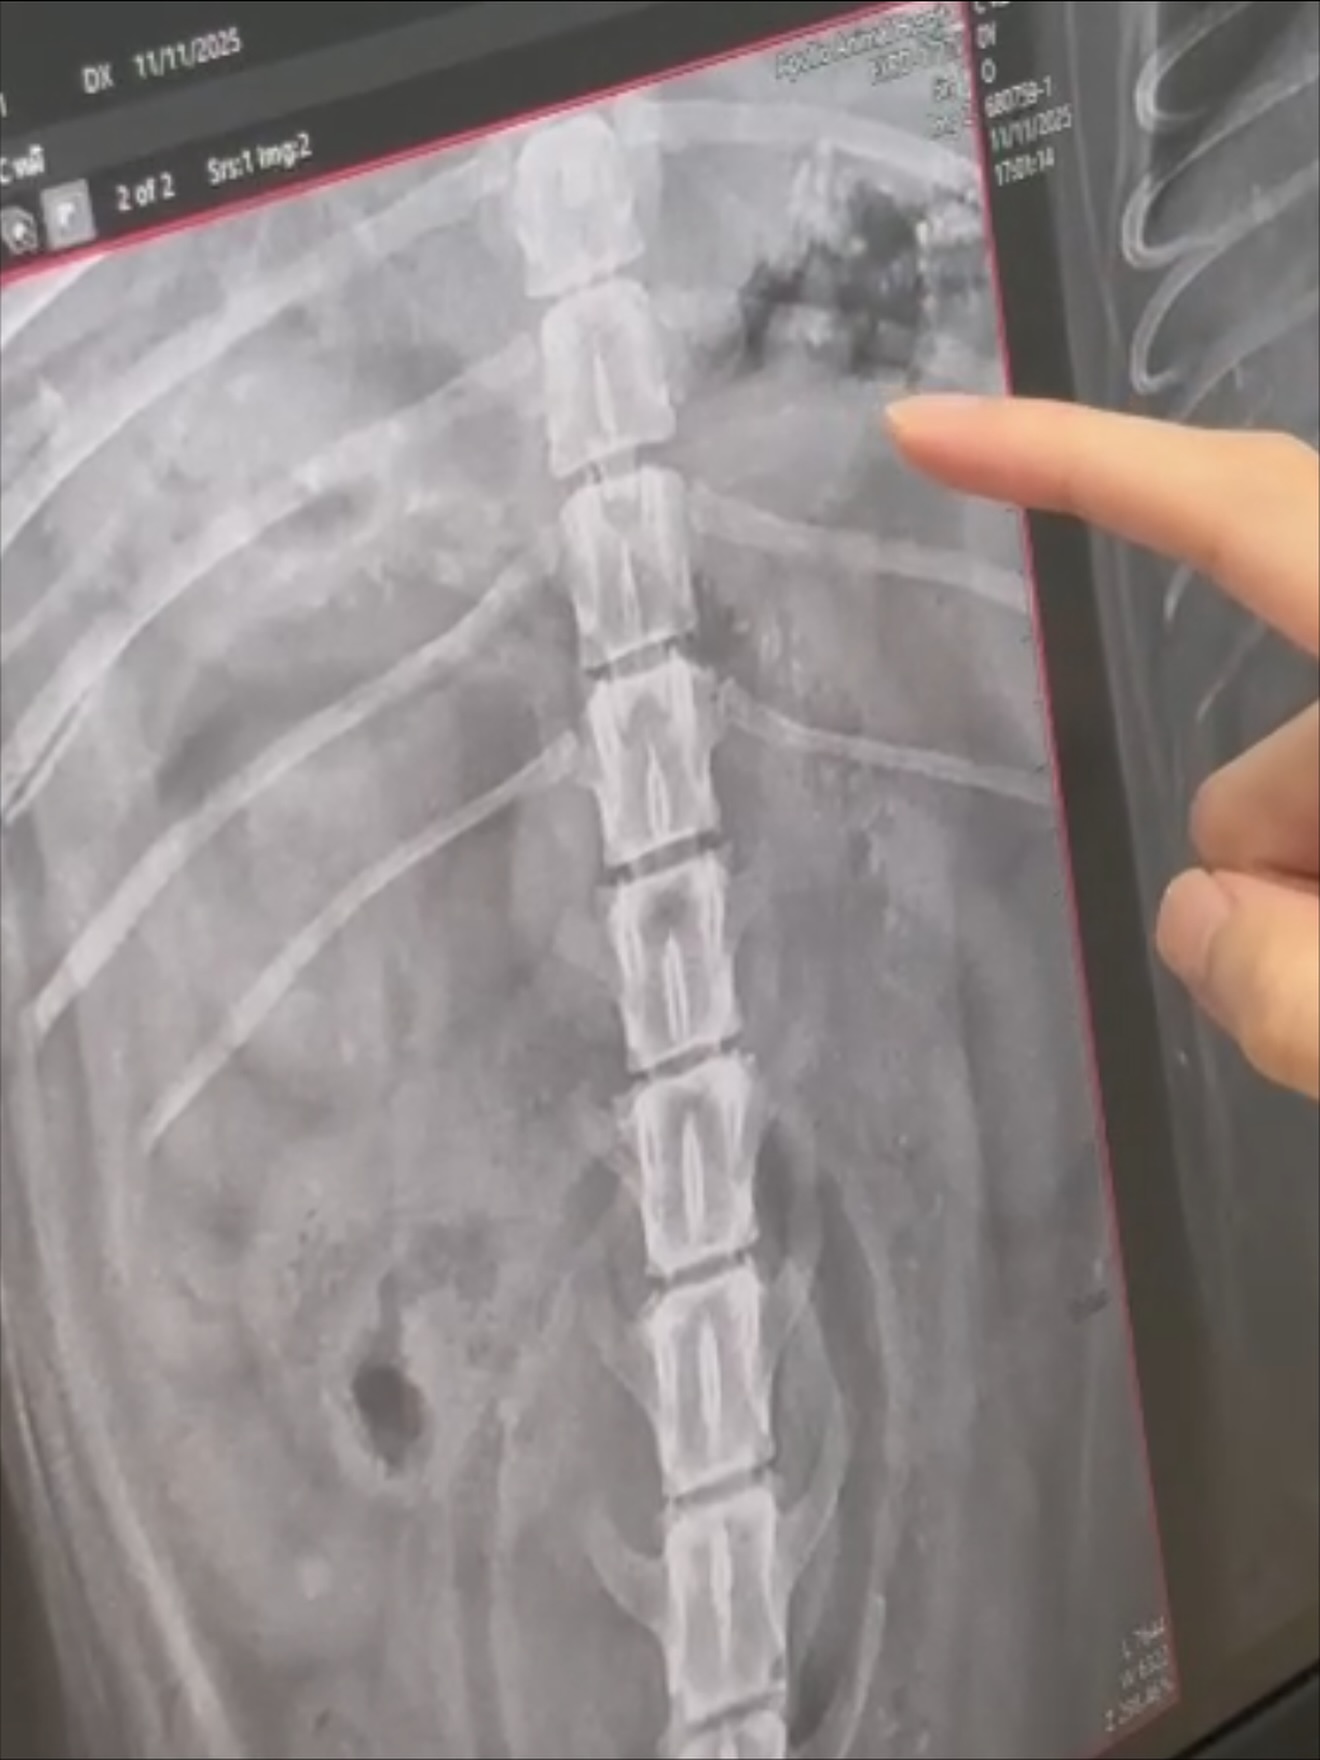

ได้ X-Ray, ส่องกล่อง และอัลตร้าซาวด์ พบว่ามีเศษที่มีลักษณะแข็งคล้ายกระดูกและไม้

กระจายอยู่เต็มกระเพาะอาหาร ลักษณะมีทั้งสีขาวแหลมเป็นก้อนแข็ง คล้ายกระดูก ปูน,

สีดำและสีน้ำตาลคล้ายเศษไม้ คุณหมอได้ทำการล้างท้อง แต่เศษดังกล่าว

ยังคงติดค้างอยู่ในบริเวณท้องตอนนี้แพทย์กำลังดำเนินการรักษาอย่างต่อเนื่อง